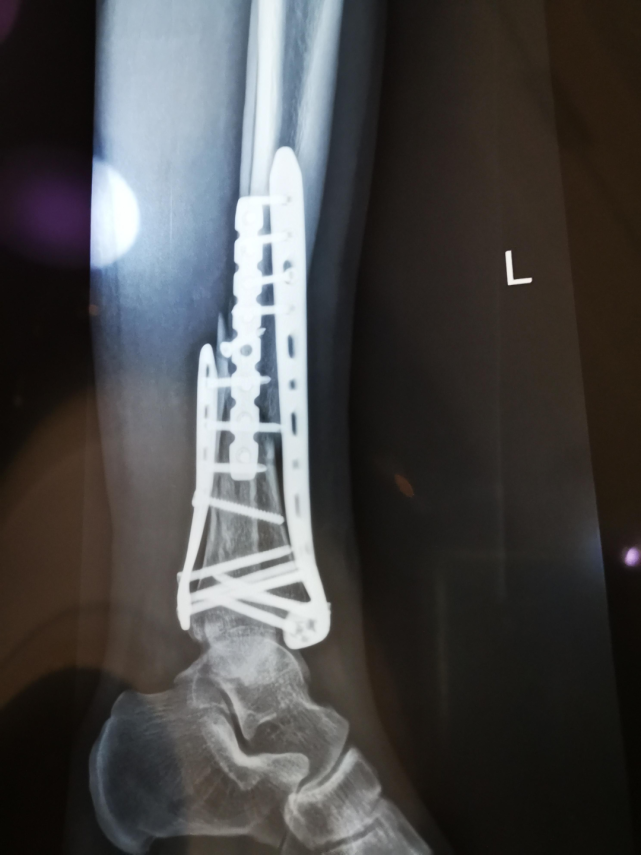

片子里,三块钢板挤在我的小腿断骨处,十几二十颗钢钉横七竖八、张牙舞爪地插在里面。爱人戏称这是“咸菜(钢钉)炒肉丝,只见咸菜不见肉”。

图片

术后3天复查的X线片丨作者供图

医生拿起片子,耐心地对我们解释手术情况:“手术时,我先让你趴着做的踝关节,那里的骨头碎了,但好在移位不多。因为你的骨折是扭伤造成的,胫腓骨断裂的裂痕比较长,所以一块钢板不够,只能放三块。手术很成功。”